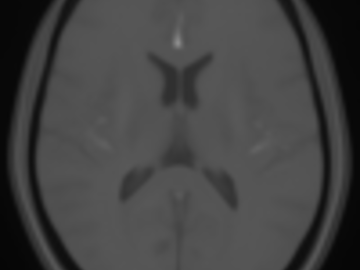

FLAIR and NCCT atlases for the elderly

Normative brain atlases are a standard tool for neuroscience research and are, for example, used for spatial normalization of image datasets prior to voxel-based analyses of brain morphology and function. Although many different atlases are publicly available, they are usually biased with respect to an imaging modality and the age distribution. Both effects are well known to negatively impact the accuracy and reliability of the spatial normalization process using non-linear image registration methods. An important and very active neuroscience area that lacks appropriate atlases is lesion-related research in elderly populations (e.g. stroke, multiple sclerosis) for which FLAIR MRI and non-contrast CT are often the clinical imaging modalities of choice. To overcome the lack of atlases for these tasks and modalities, this paper presents high-resolution, age-specific FLAIR and non-contrast CT atlases of the elderly built from clinical images.

We provide an asymmetric and symmetric version of both the FLAIR and NCCT atlases in the standard MNI coordinate system with binary masks for the brain volume. We also provide the deformation field to map parcellations in the MNI space to our atlases (both symmetric and asymmetric) should researchers require this in their individual research projects.